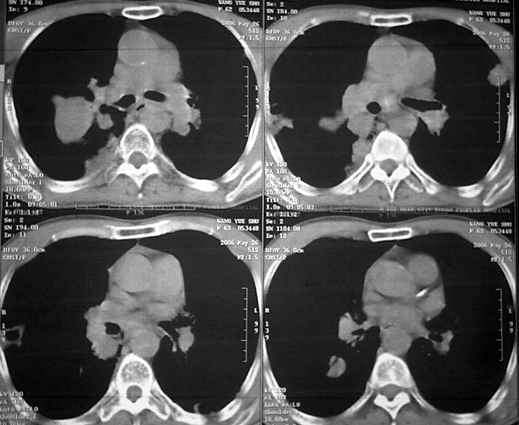

男62肺癌治疗后复查

具体治疗措施不清楚,治疗前空洞很少,请讨论空洞的性质

双肺内及胸壁旁见有多发软组织实性阴影和空洞,实性病变多见有脐凹切迹,贴近胸膜的见有胸膜凹陷征;空洞的壁多为厚薄不均,形态不规则,纵隔内见有较多肿大淋巴结,诊断为双肺内转移性病变。

双肺内及胸壁旁见有多发软组织实性阴影和空洞,实性病变多见有脐凹切迹,贴近胸膜的见有胸膜凹陷征;空洞的壁多为厚薄不均,形态不规则,纵隔内见有较多肿大淋巴结,诊断为双肺内转移性病变。[气囊或孔洞实为腺癌缘肺泡壁生长所致]

3.3 cpm的ct特征

cpm灶多为圆形或类圆形、无分叶和毛刺,说明除空洞外cpm 基本保留了转移瘤的形态特点。本组中单个病例出现cpm灶1 16枚,多发与单发者大致相等,说明cpm瘤灶的数目变化大。全部病例的cpm灶均是与肺内多发实性瘤灶共存,而且后者往往远多于前者。另外,当病情好转或恶化时,cpm灶与实性瘤灶同时缩小或增大,说明两者呈同步变化。笔者认为这两点是cpm 最恒定的ct特点。•

单个cpm灶的空洞形态具有多样性,壁可薄可厚,厚度可均匀可不均匀,瘤灶大小变化也大。但总的说来,cpm 的洞壁较薄,4mm以下者最多(53%),其次为4—15mm者(34%),而15mm以上者却较少。另外洞壁厚度均匀者也较多(47%)。笔者认为这些与壁薄而均匀的囊样及小环形空洞较多有关。一般认为壁薄而均匀者多为良性空洞,而癌性空洞的壁多较厚或厚薄不均。woodring等-8 j认为洞壁厚度4mm以下者92%为良性,15mm 以上者95%为恶性,15mm者良恶性各半。蒋瑾等-9 j发现83% 的原发空洞型肺癌的壁厚度超过15mm。以上说明cpm的空洞形态不同于肺良性空洞及原发癌性空洞,具有其独特性。本组40%(16/40)的病例中同时存在多种空洞,说明cpm病例具有空洞类型的混合性。同样的洞腔变化既可见于病情好转时,也可见于病情恶化时,特别是同一种病例可同时出现两种相反的洞腔变化,说明洞腔变化具有非恒定性。

右肺门软组织块影,右主支气管及中间段支气管管壁明显增厚,两肺内多发结节及大小不等的类圆形薄壁空洞,纵隔内多发肿大的淋巴结;

考虑:1.右中央型肺癌伴两肺广泛性转移及纵隔转移。